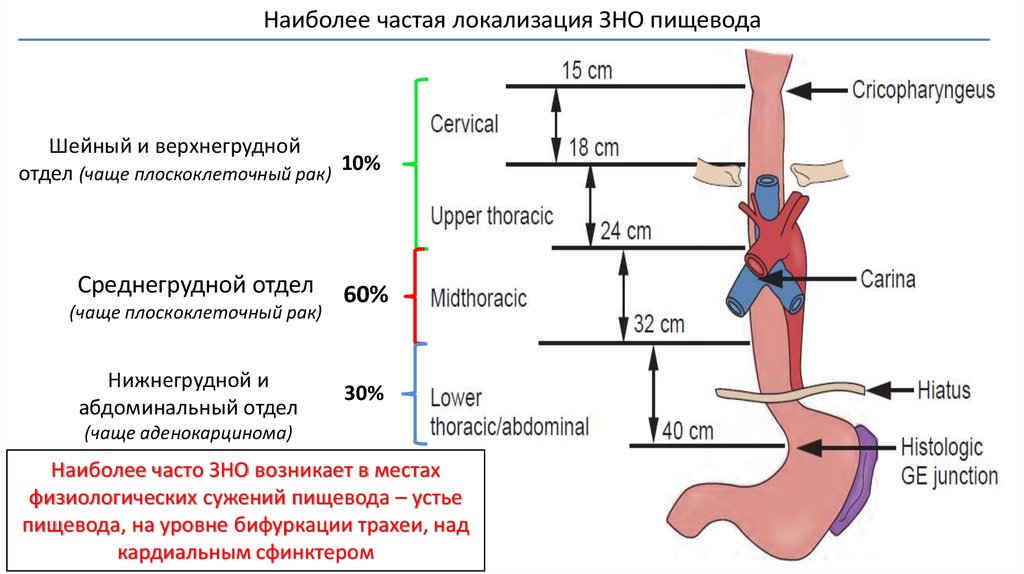

Злокачественные новообразования шейного отдела пищевода, выбор пластики